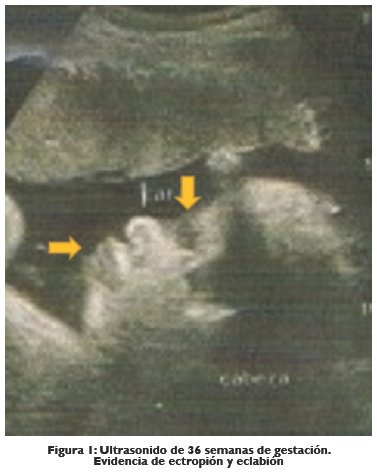

En el ultrasonido obstétrico de control prenatal realizado a las 37,3 semanas de gestación se describen presencia de ectropión bilateral (Eversión de parpados) y eclabión (Eversión de labios), características físicas de una ictiosis congénita (ver Fig. 1).